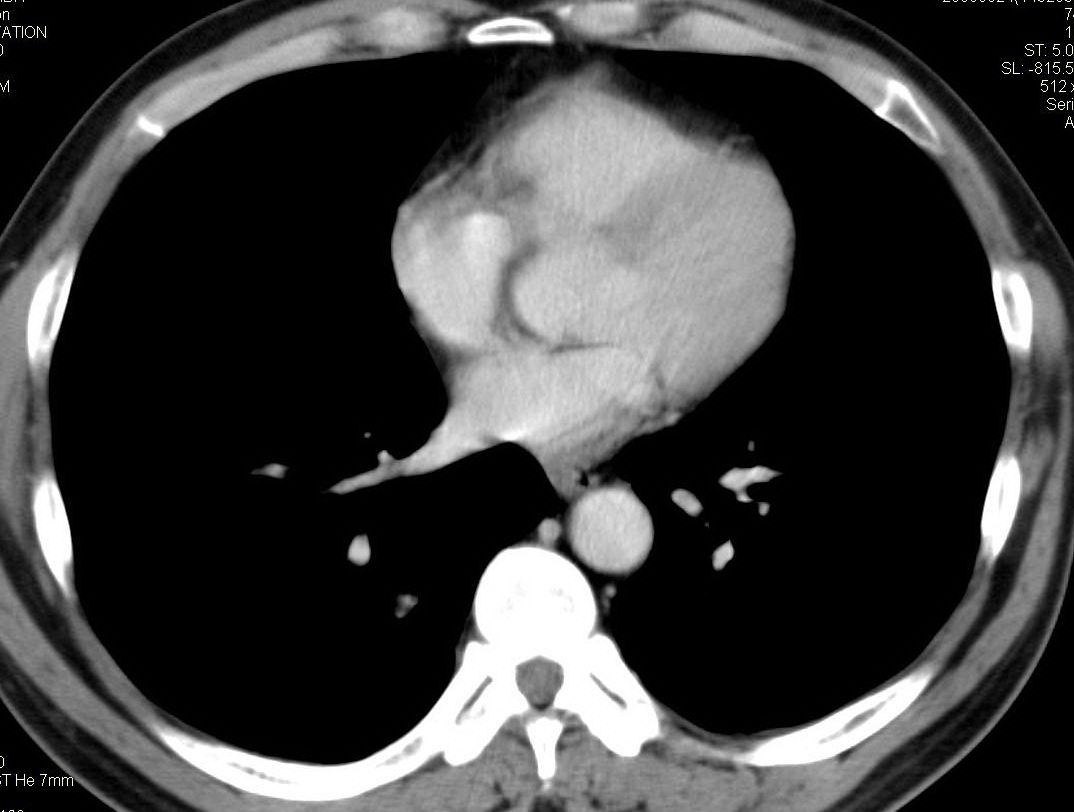

标题: CT15857:男性 58岁 咳痰带血 无发热 请各位大侠发表一下意见 [打印本页]

标题: CT15857:男性 58岁 咳痰带血 无发热 请各位大侠发表一下意见

两肺下叶肺纹理增多、增粗并呈“树芽状”改变。支气管扩张呈囊状,部分呈柱状改变。其周围可见散在的斑片样及条索样密度增高影,右肺下叶近叶间胸膜可见一形态不规则的高密度结节影,并与胸膜粘连。

考虑:支扩并发感染。

双肺多发炎性病灶,结核可能性大,建议抗炎治疗复查.右肺下叶前基底段结节灶,高度警惕肺癌可能

双肺间质性改变(间质纤维化?)伴支扩。右肺下叶有毛刺的小结节,考虑周围型肺癌可能性。